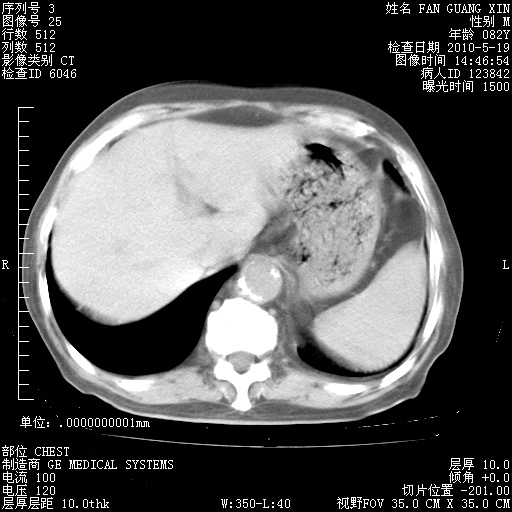

还需要哪些辅助检查?我们医院排除真菌感染没有任何检验方法,胸片好像能够排除肺部真菌感染。